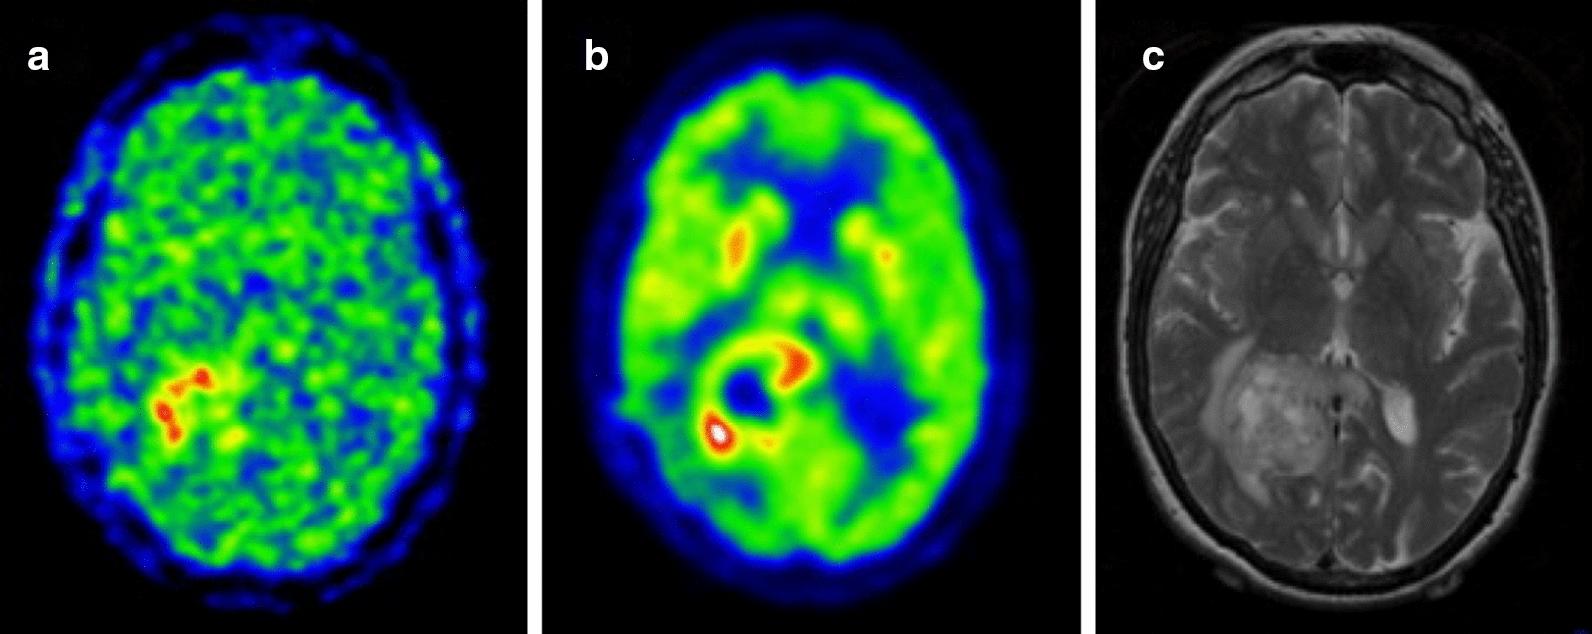

Over the last few years, cancer immunotherapy experienced tremendous developments and it is nowadays considered a promising strategy against many types of cancer. However, the exclusion of lymphocytes from the tumor nest is a common phenomenon that limits the efficiency of immunotherapy in solid tumors. Despite several mechanisms proposed during the years to explain the immune excluded phenotype, at present, there is no integrated understanding about the role played by different models of immune exclusion in human cancers. Hypoxia is a hallmark of most solid tumors and, being a multifaceted and complex condition, shapes in a unique way the tumor microenvironment, affecting gene transcription and chromatin remodeling. In this review, we speculate about an upstream role for hypoxia as a common biological determinant of immune exclusion in solid tumors. We also discuss the current state of ex vivo and in vivo imaging of hypoxic determinants in relation to T cell distribution that could mechanisms of immune exclusion and discover functional-morphological tumor features that could support clinical monitoring.

在过去的几年中,癌症免疫疗法取得了巨大的发展,如今被认为是对抗多种癌症的有前途的策略。然而,淋巴细胞从肿瘤巢中被排除是一种常见的现象,限制了免疫疗法在实体瘤中的效率。尽管多年来提出了几种机制来解释免疫排除表型,但目前对于不同的免疫排除模型在人类癌症中所起的作用还没有一个综合的认识。缺氧是大多数实体瘤的一个标志,并且作为一种多方面和复杂的情况,以独特的方式塑造肿瘤微环境,影响基因转录和染色质重塑。在这篇综述中,我们推测缺氧作为实体瘤中免疫排除的共同生物学决定因素具有上游作用。我们还讨论了目前关于缺氧决定因素的离体和在体成像与 T 细胞分布的关系,这可能有助于发现免疫排除的机制和发现支持临床监测的功能形态学肿瘤特征。